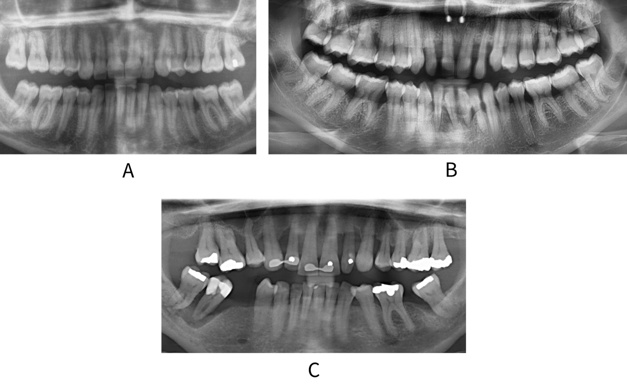

The extent/distribution of disease is a measure of how many teeth in the dentition have been affected by periodontitis (see Figure: Extent/distribution of disease). It is determined by assessing what proportion of teeth in the dentition have lost supporting bone (see table: Extent/distribution of bone loss).

Extent/distribution of disease

A: Radiograph showing localised bone loss. B: Radiograph showing molar incisor pattern bone loss. C: Radiograph showing generalised periodontitis with >30% of teeth affected by bone loss.